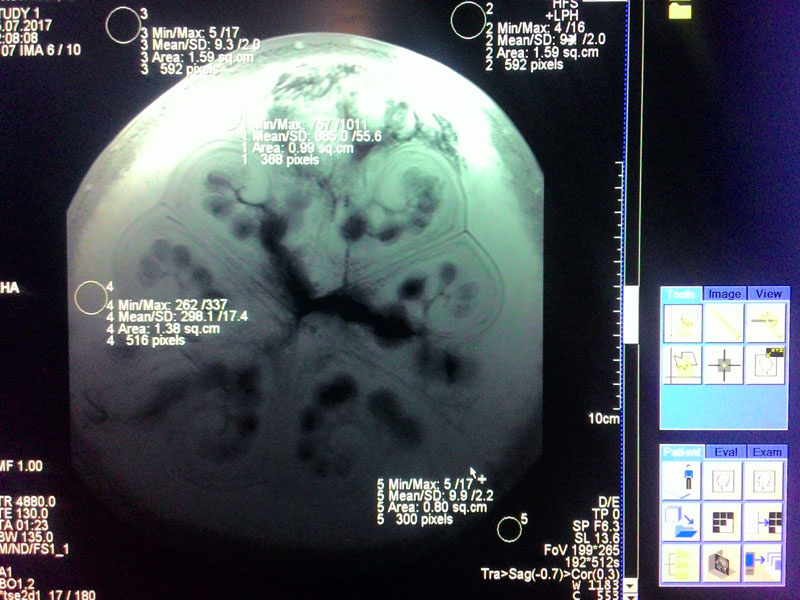

Арбуз готовится к исследованию. На нем сверху лежит катушка, предназначенная для грудной области, под ним — катушка для спинного отдела и позвоночника. Справа на полу — шар для предсказаний специальный объект для калибровки систем аппарата, так называемый «фантом»

Мало кто режет арбузы в поперечном направлении. Аппарат МРТ позволяет сделать это без ножа. Знали ли вы об интересной фрактальной структуре внутри? Обратите внимание, что верхняя часть, которая ближе к приемным элементам катушки светлее, так как амплитуда сигнала, получаемого из этой области выше, чем снизу ягоды.

Продольный разрез уже знаком всем. Думаю, арбуз спелый, можно брать.